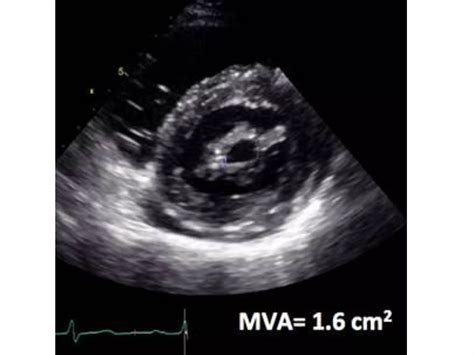

Valve Area: The area of the mitral valve opening is measured. A normal valve area is typically around 4-6 cm². In mitral stenosis, this area is significantly reduced, often to less than 2 cm².